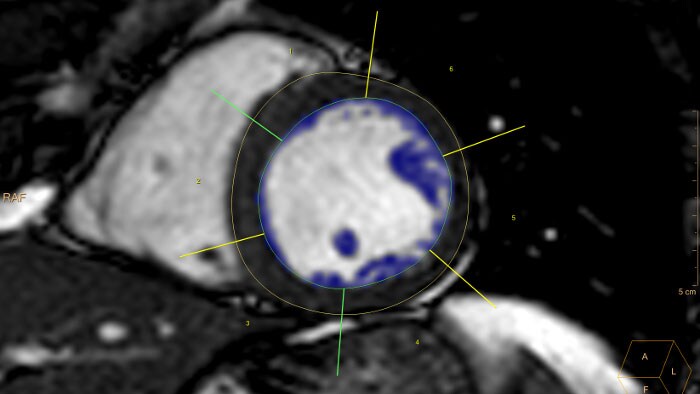

RM cardíaca

Permite a visualização de uma única, de múltiplas ou de todas as séries cardíacas disponíveis, incluindo a sincronização das fases cardíacas.